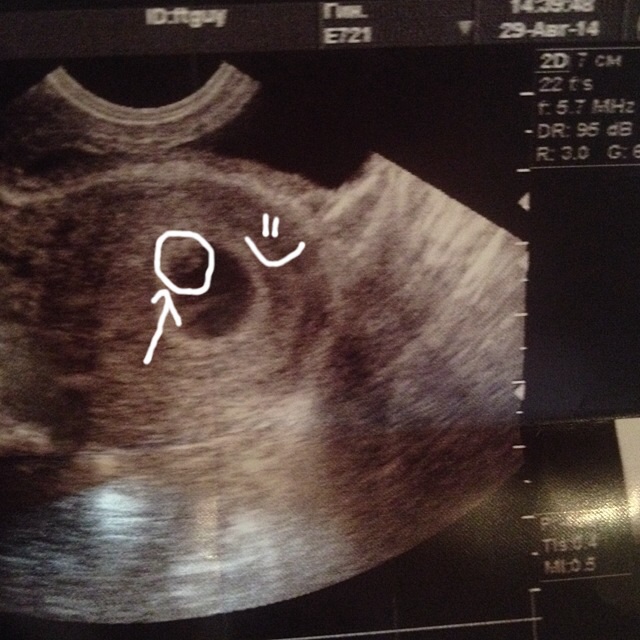

Всем привет, сегодня сходили к гинекологу, сто процентов беременна, нам 5-6 неделек уже!)))))

Сделали узи, вот наша первая фотография, мы еще совсем маленькие, 2мм примерно!!!

Я видела как сердечко билось у малыша!!!! Просто счастья полные штаны!!!